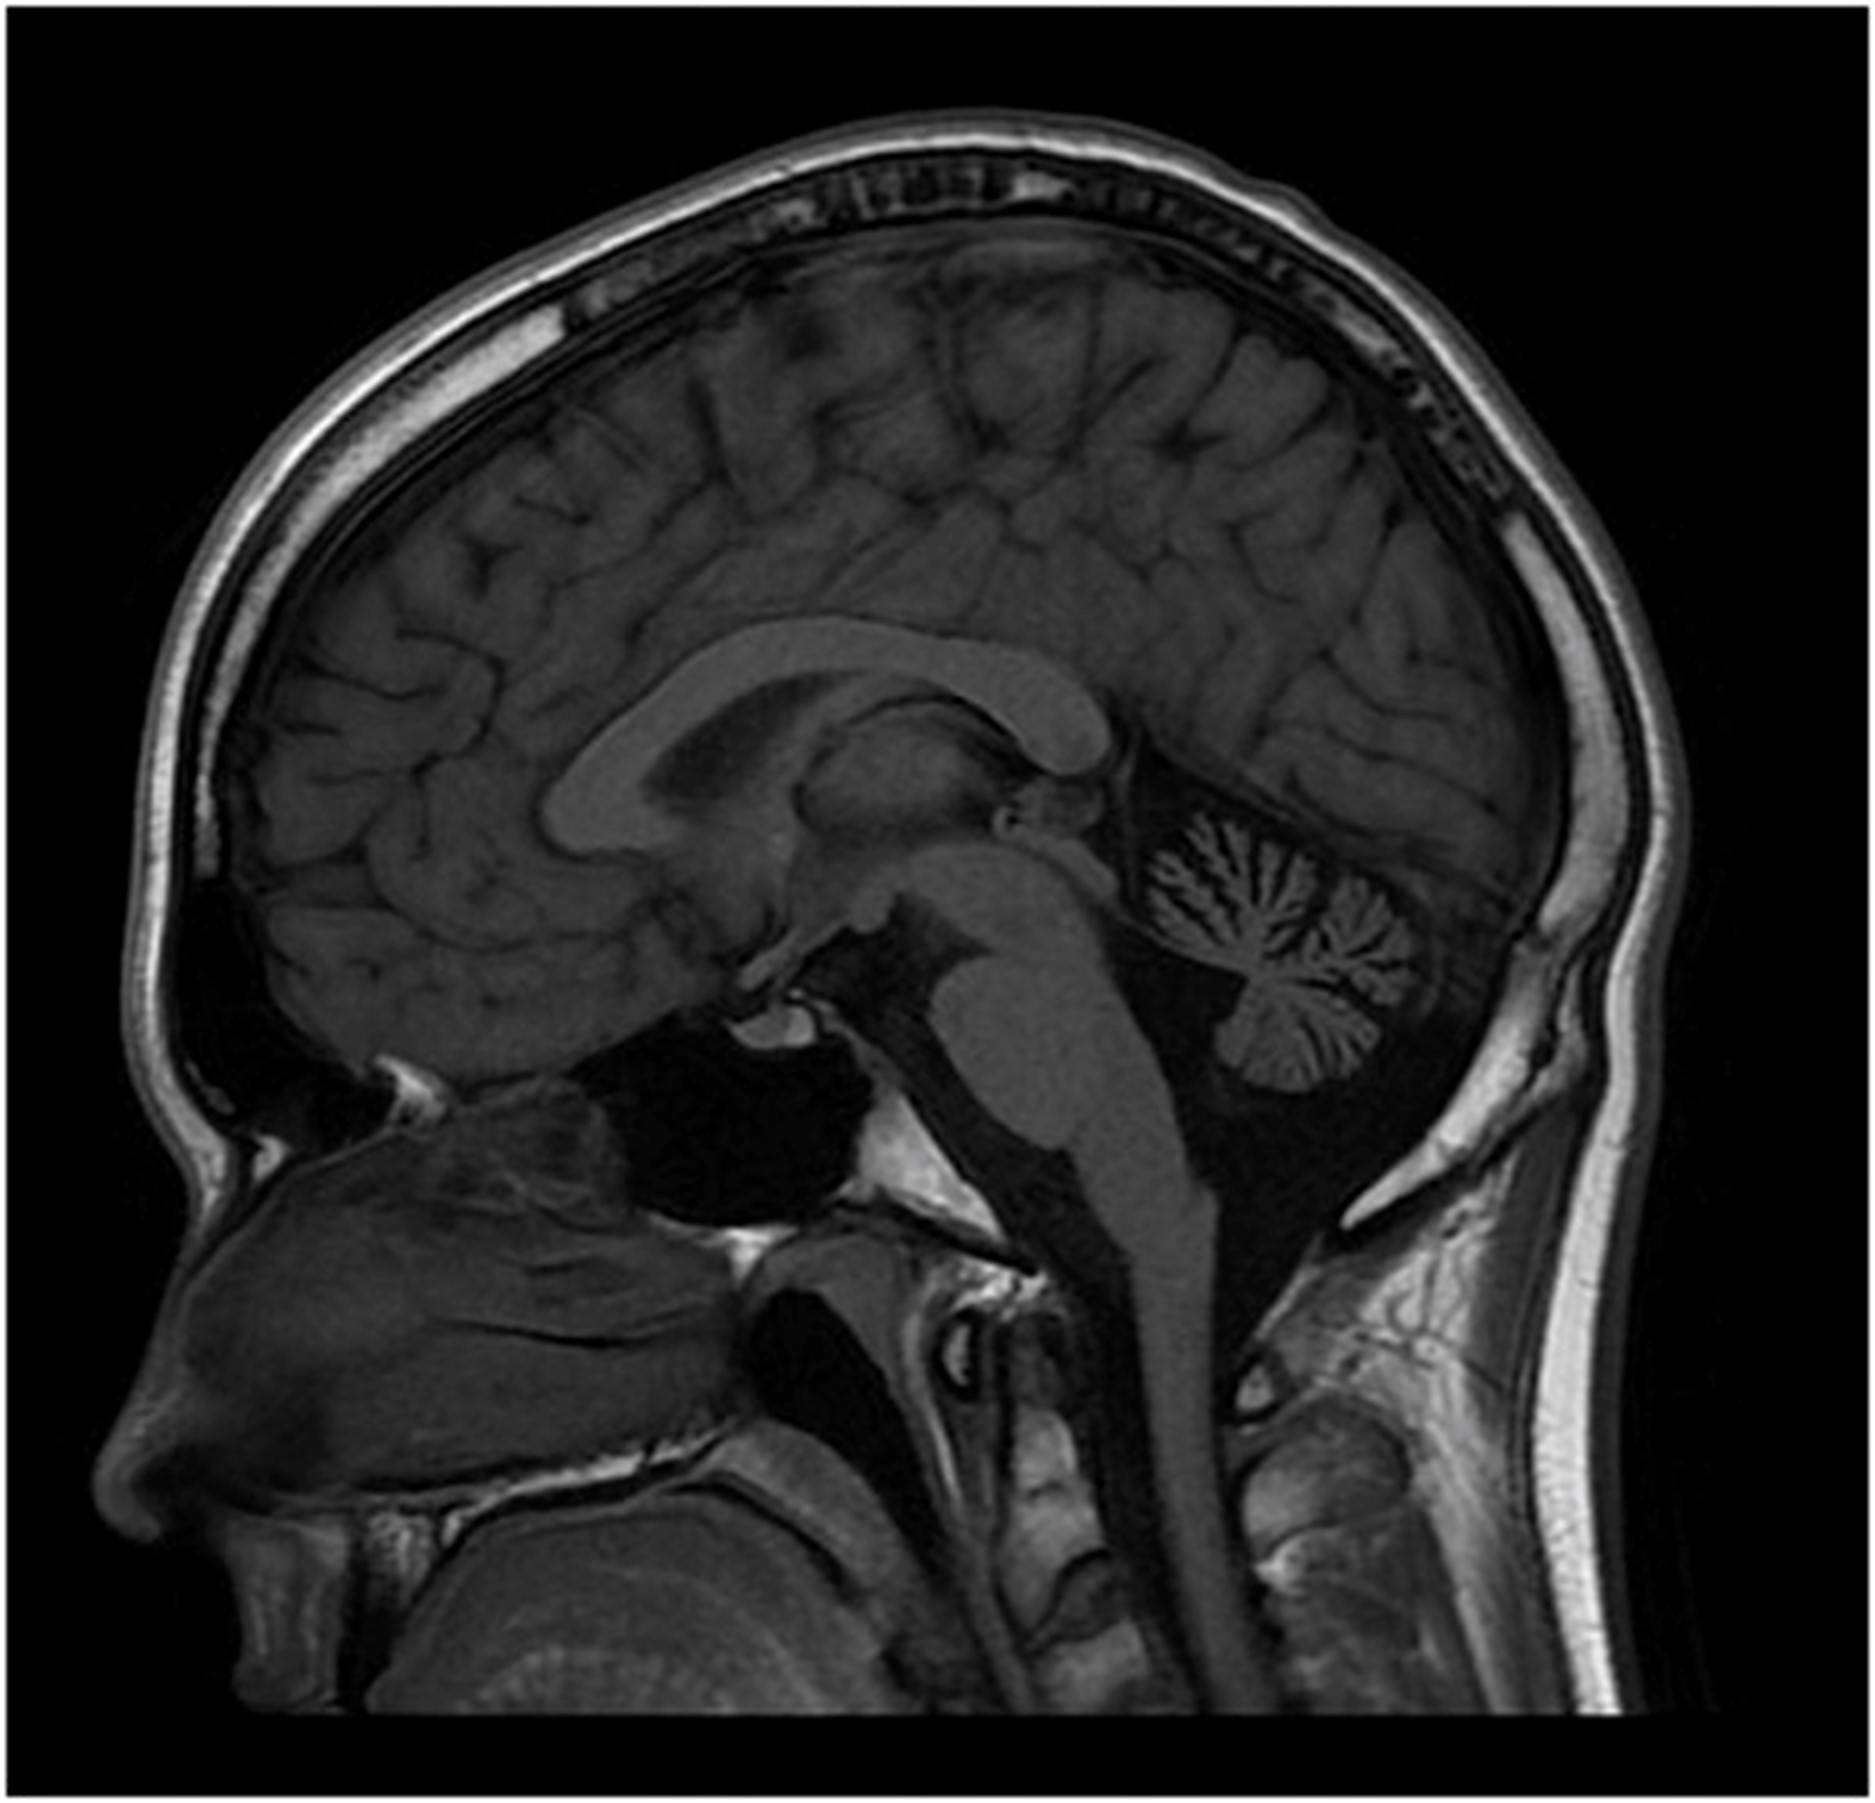

12 岁时脑部 MRI 显示小脑萎缩(图2). 在几年的时间里进行了广泛的基因检测和代谢测试,包括正常PMP22重复/缺失分析基因检测、MPZ、GJB1、PMP22和c10orf2基因检测、脊髓小脑性共济失调组(SCA 1、2、3、6、7、8、17 ), Friedreich 共济失调重复基因检测和血清维生素 E 水平。染色体微阵列基因检测正常。肌肉活检(15 岁时)显示轻微的神经源性变化。肌肉呼吸链酶检测正常。血浆肾上腺和睾丸性类固醇水平正常。